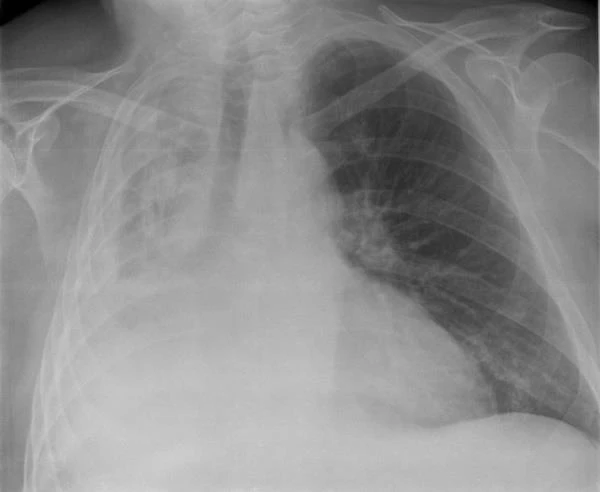

Ảnh chụp X-quang của một người bị sụp phổi. Ảnh: SCMP

Tràn khí màng phổi là khi có một lượng không khí bất thường trong khoang màng phổi giữa phổi và thành ngực. Các triệu chứng thường bao gồm đột ngột đau nhói, đau một bên ngực và khó thở. Trong một số ít trường hợp, lượng không khí trong ngực tăng lên khi van một chiều được hình thành bởi một vùng mô bị tổn thương, dẫn đến tràn khí màng phổi căng.

Tình trạng này có thể gây ra tình trạng thiếu ôxy trầm trọng và huyết áp thấp. Trừ khi đảo ngược bằng cách điều trị hiệu quả, nó có thể dẫn đến tử vong. Rất hiếm khi cả hai phổi có thể bị ảnh hưởng bởi tràn khí màng phổi.